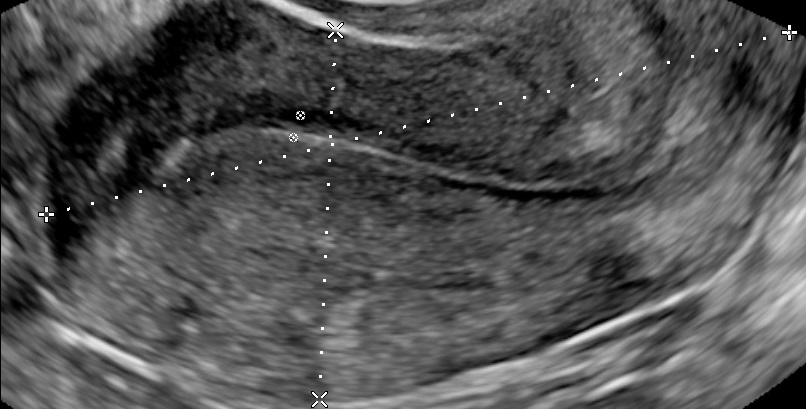

- Characteristics associated with adenomyosis according to the MUSA criteria (enlarged globular uterus, asymmetrical thickening of the myometrium, myometrial cysts, echogenic subendometrial lines and buds, hyperechogenic islands, fan shaped shadowing, an irregular or interrupted junctional zone, and translesional vascularity on color Doppler)

- Location (anterior, posterior, lateral left, lateral right or fundal)

- Focal, diffuse, mixed-type, or adenomyoma (focal adenomyosis refers to cases where less than 25% of the myometrium of the corpus uteri is involved and more than 25% of the circumference of the lesion is surrounded by normal myometrium, estimated on that sagittal uterine section where the adenomyotic lesion appears the largest. When focal adenomyosis is distinctly demarcated and surrounded by hypertrophic myometrium, it is called an adenomyoma.)

- Cystic or non-cystic (cysts at least 2mm)

- Myometrial layer involvement (type 1: the junctional zone, type 2: the middle myometrium, type 3: the outer myometrium – the layer between the serosa and the vascular arcade)

- Disease extent (mild: <25% of uterine volume, moderate: 25-50% or severe: >50%)

- Lesion size